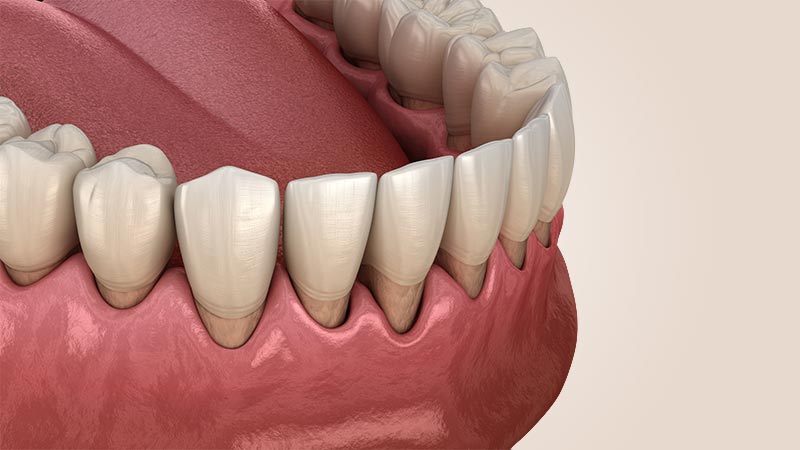

DİŞ ETİ ÇEKİLMESİ

Diş eti çekilmeleri çok farklı nedenler ile ve çok farklı şekiller ile karşımıza çıkmaktadır.

Diş eti iltihabına bağlı olarak meydana gelen diş eti çekilmeleri çoğunlukla dişler etrafında kemik kayıpları ile birlikte seyretmektedir ve bu diş eti çekilmelerinde kaybedilen dokuların geri yerine getirilmesi çok kısıtlı durumlarda mümkün olabilmektedir. Bu diş eti çekilmelerinin varlığında yapılması gereken tedavi, diş eti çekilmelerinin durdurulmasına yönelik olmaktadır.

Bazı durumlarda ise, diş eti çekilmelerini tamamen geri döndürmek mümkündür. Uzun frenulum bağlantılarına bağlı olarak ya da hatalı diş fırçalama gibi nedenler ile meydana gelmiş olan diş eti çekilmelerinin diş eti operasyonları ile birlikte geri kazandırılması mümkündür.

Serbest Diş Eti Grefti Operasyonu

Diş eti çekilmelerinin tedavisinde yapılan operasyonlardan bir tanesidir. Diş eti çekilmesinin olduğu bölgeye damaktan alınan diş etinin yerleştirilmesi ile gerçekleştirilir.

Bağ Dokusu Grefti Operasyonları

Diş eti çekilmelerinin tedavisinde uygulanan yöntemlerden bir tanesidir. Diş eti çekilmesinin olduğu bölgeye damaktan alınan diş etinin yerleştirilmesi ile gerçekleştirilir.